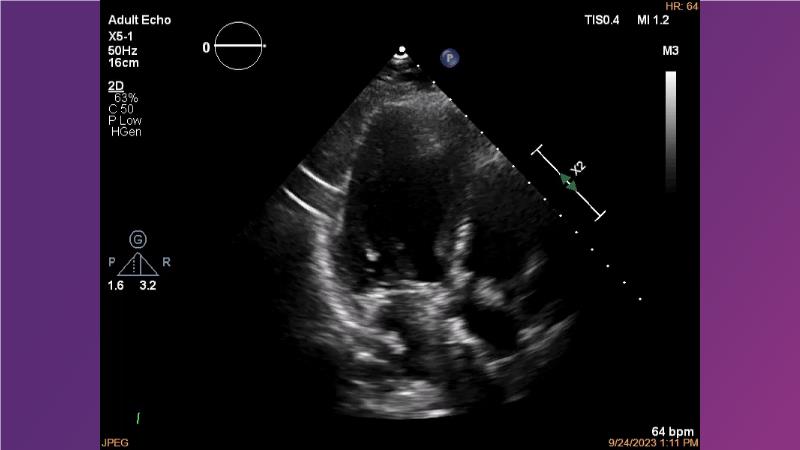

Gain expertise in selecting the appropriate TAVI device for achieving stable deployment in a 90-degree horizontal aorta. Discover techniques for ensuring smooth deliverability, particularly when navigating through tight and tortuous anatomies. Additionally, learn strategies to prepare for future coronary access, irrespective of the height of the left or right coronaries.

• To learn how to select your TAVI device in order to achieve stable deployment in 90 degrees horizontal aorta